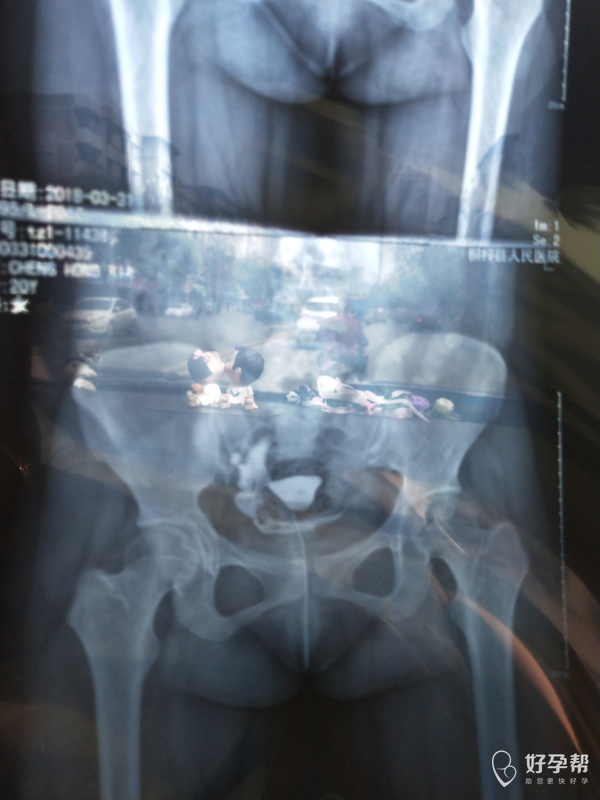

医生 看看我的输卵管造影

输卵管堵塞一是手术,二是试管婴儿。建议直接试管婴儿。